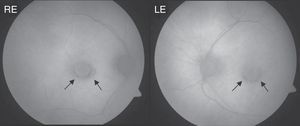

Clinical CaseThe patient was a 64-year-old woman being treated for rheumatoid arthritis, who had ingested a cumulative total dose of 112g of hydroxychloroquine at a rate of 400mg daily for the first 60 days and 200mg daily for the remaining 1380 days. She had a history of chronic liver disease, so was undergoing semi-annual follow up visits in our ophthalmology department since the start of treatment. At the time of diagnosis of antimalarial maculopathy, she exhibited a 0.7 best corrected visual acuity in both eyes. Perimetry showed bilateral paracentral scotoma and fundoscopy observed concentric hypopigmentation and hyperpigmentation appreciated in both macula, most evident in the retinography with autofluorescence (Fig. 1). The optical coherence tomography (OCT) image showed characteristic “flying saucer” lesions in both eyes (Fig. 2) and the central multifocal electroretinography (ERGmf) appreciated a decrease in amplitude, definition and density of electrical waves (Fig. 3A). We immediately suspended hydroxychloroquine treatment and the patient was started one tablet daily of a complex of antioxidants and vitamins, usually employed in macular degeneration associated with age. An ERGmf at 12 months after the discontinuation of therapy detected a surprising improvement (Fig. 3B) with an increase in the amplitude of the central hexagon of 67% in the right eye and 104% in the left. Similarly, the amplitude ratio between the central and pericentral ring, increased from 1.2 to 2.3 in the right eye and 1.9 to 3.1 in the left. The defective resolution of ERGmf waves obtained at the time of detection of the antimalarial maculopathy (Fig. 3A) prevents a reliable determination of the implicit times and their comparison with the record made after one year. The improvement was reflected in a recovery of best corrected visual acuity in the right eye, with maintenance of vision in the left eye at 0.7. The fundus images and the “flying saucer” lesions on the OCT were not modified.